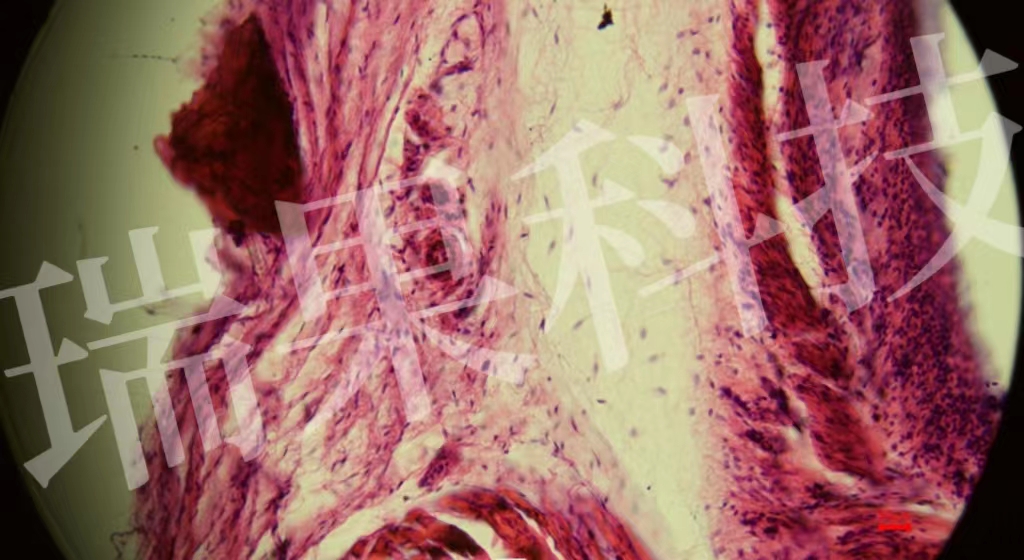

HE染色:蘇木精 - 伊紅染色法 ( hematoxylin-eosin staining ) ,簡(jiǎn)稱HE染色法 ,石蠟切片技術(shù)里常用的染色法之一 。蘇木精染液為堿性 ,主要使細(xì)胞核內(nèi)的染色質(zhì)與胞質(zhì)內(nèi)的核酸著紫藍(lán)色 ;伊紅為酸性染料 ,主要使細(xì)

HE染色:蘇木精 - 伊紅染色法 ( hematoxylin-eosin staining ) ,簡(jiǎn)稱HE染色法 ,石蠟切片技術(shù)里常用的染色法之一 。蘇木精染液為堿性 ,主要使細(xì)胞核內(nèi)的染色質(zhì)與胞質(zhì)內(nèi)的核酸著紫藍(lán)色 ;伊紅為酸性染料 ,主要使細(xì)胞質(zhì)和細(xì)胞外基質(zhì)中的成分著紅色 。HE染色法是組織學(xué)、胚胎學(xué)、病理學(xué)教學(xué)與科研中最基本、使用最廣泛的技術(shù)方法。

視網(wǎng)膜

心1-1-20x

血清粘液腺-20x